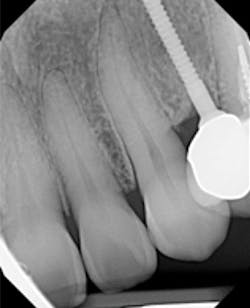

A 1.8 mm x 14 mm Anew implant (Dentatus) was selected, and a surgical guide was fabricated for a flapless approach. In this instance, a healing cap was placed, and the existing flipper was relieved to address financial concerns (figures 9 and 10). A screw-retained crown was fabricated three months post insertion (figures 11 and 12). The patient reported no postoperative discomfort, and the case remains successful, as shown in the two-year postoperative x-ray (figure 13).

Figure 13: Two-year follow-up